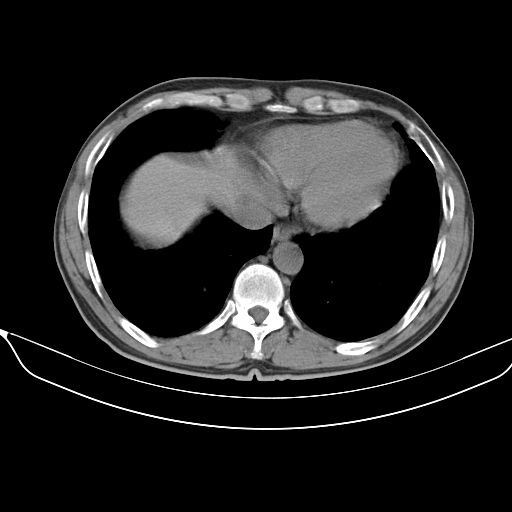

以下是引用心路寻觅在2010-3-1 10:23:00的发言:[br]1、考虑左肺上叶周围型肺癌[br]2、右上肺陈旧性病灶。[br][br][本贴已被 心路寻觅 于 2010-3-1 10:40:18 修改过]

以下是引用shuiyuan在2010-3-1 10:45:00的发言:[br]考虑左肺上叶中心型肺癌伴阻塞型炎症,邻近胸膜受侵。